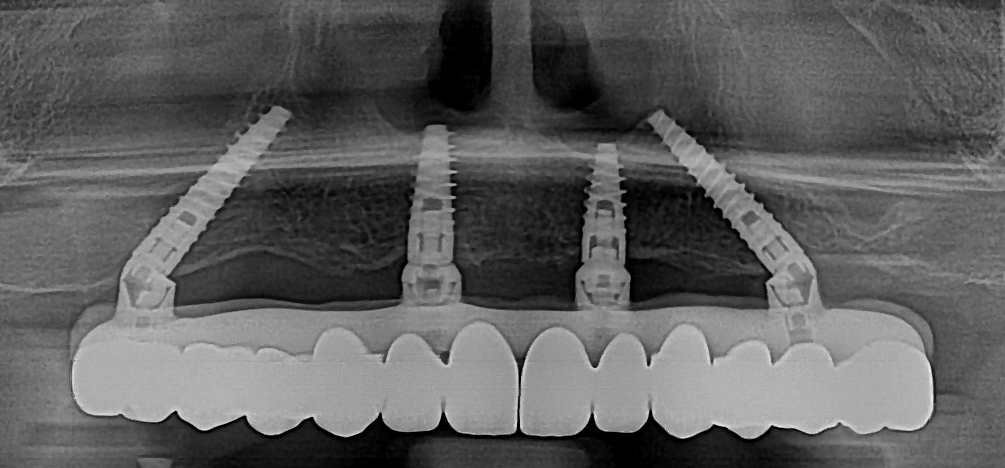

Aceasta are la bază un schelet din titan, un material de două ori mai ușor decât plasticul și de zece ori mai rezistent decât alte metale. Spre deosebire de proteza provizorie, unde scheletul este realizat sub forma unei bare, la proteza definitivă fiecare dinte are locul său bine definit pe structura de titan, ceea ce oferă o stabilitate superioară.

Un alt avantaj major îl constituie dinții confecționați din ceramică, un material mult mai rezistent și mai estetic decât PMMA-ul frezat, utilizat la protezele provizorii. Acest lucru asigură nu doar o durabilitate mai mare, ci și un aspect natural, apropiat de cel al dinților reali.

Scheletul unei proteze finale